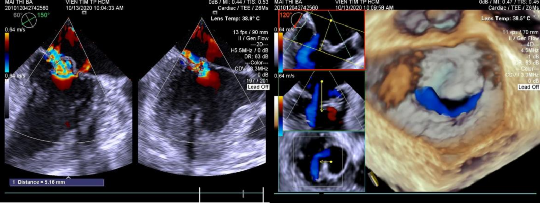

Hình 2.1: Bệnh lý hở van hai lá trên siêu âm 4D

Hình 2.2: Siêu âm hở van 2 lá Doppler màu và 4D.